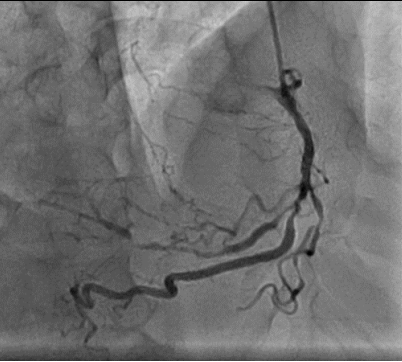

The patient then underwent elective coronary angiography which showed a Normal Left Main,  100% occluded Left Anterior Descending Artery, filling from right sided collaterals, a proximal 80% in the left circumflex with a 99% occluded OM1. The RCA had a proximal 80% lesion with a diffusely diseased acute marginal branch.

Figure 5 Tubular tight lesion prese nt in the RCA

Figure 6 The LAD being fed from collaterals from the RCA